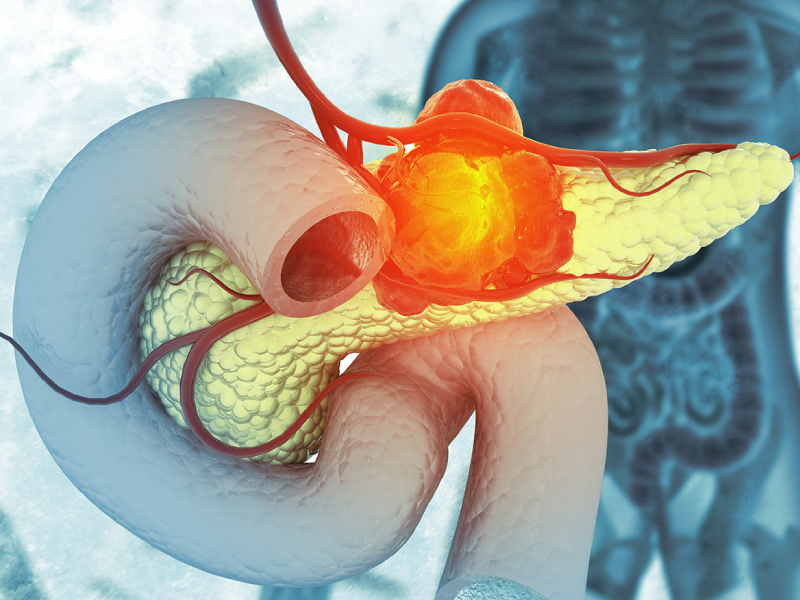

سرطان پانکراس یکی از مرگبار ترین انواع سرطانهای دستگاه گوارش محسوب میشود. پانکراس یا لوزالمعده یک...

- ۳۰ جولای ۲۰۲۵